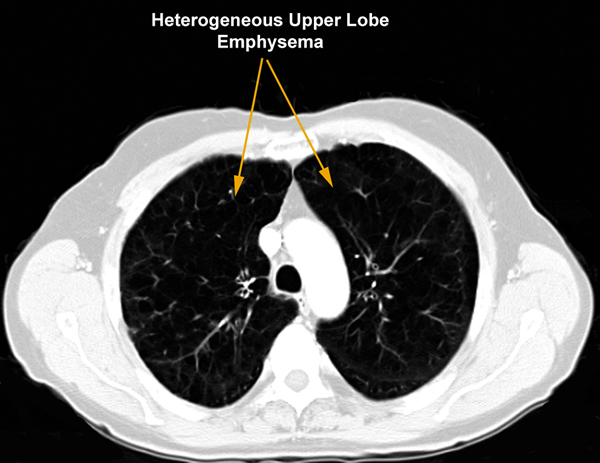

| Figure 1 |

This procedure is performed in patients with emphysema to improve their exercise tolerance and quality of life. Specific criteria were established by the National Emphysema Treatment Trial (NETT) published in 2003. An FEV1 greater than 20% predicted, DLCO greater than 20% predicted, predominantly upper lobe heterogenous distribution of emphysema on CT scan (Figure 1), matching perfusion defect on V/Q scan, low exercise tolerance or less than 40 watts exercise capacity on bicycle exercise testing, and a normal CO2 are all criteria that should be satisfied in selecting patients who will benefit from the procedure [1]. Cooper et al. have established their own set of selection criteria (Table 1) [2].